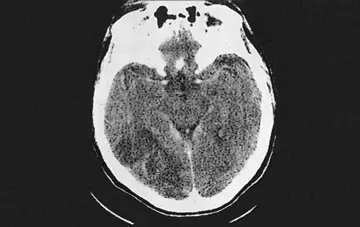

هماتولوژی - صفحه 4